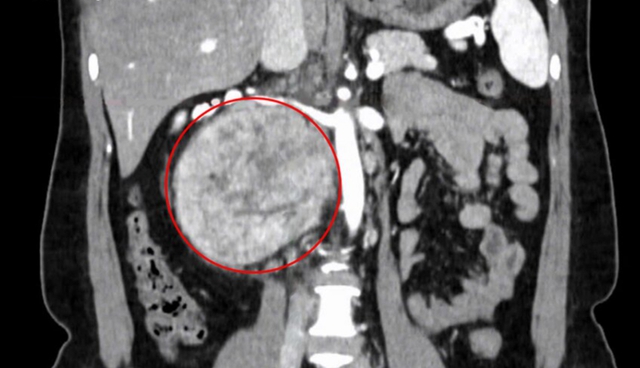

Khối u “khổng lồ” sau phúc mạc. Ảnh: BVCC

"Khối u rất lớn, kích thước 12 cm nằm sau tĩnh mạch chủ, cạnh động mạch và hai tĩnh mạch thận, gây chèn ép các cơ quan lân cận, chúng tôi phải tiến hành mổ mở để lấy trọn khối u một cách tốt nhất cho người bệnh", TS.BS Nguyễn Hoàng Đức, Trưởng khoa Tiết niệu, Trung tâm Tiết niệu – Thận học – Nam khoa cho biết.

2 tuần trước, chị Ngà đến Bệnh viện Đa khoa Tâm Anh TP.HCM khám sức khỏe tổng quát, kết quả chụp cắt lớp vi tính (CT Scan) vùng bụng phát hiện một khối u rất lớn ở vùng sau phúc mạc – là những khối u bất thường xuất hiện giữa khoang ổ bụng và cột sống lưng, thường phát sinh từ mô, thần kinh, tế bào mầm hoặc các nang sau phúc mạc.